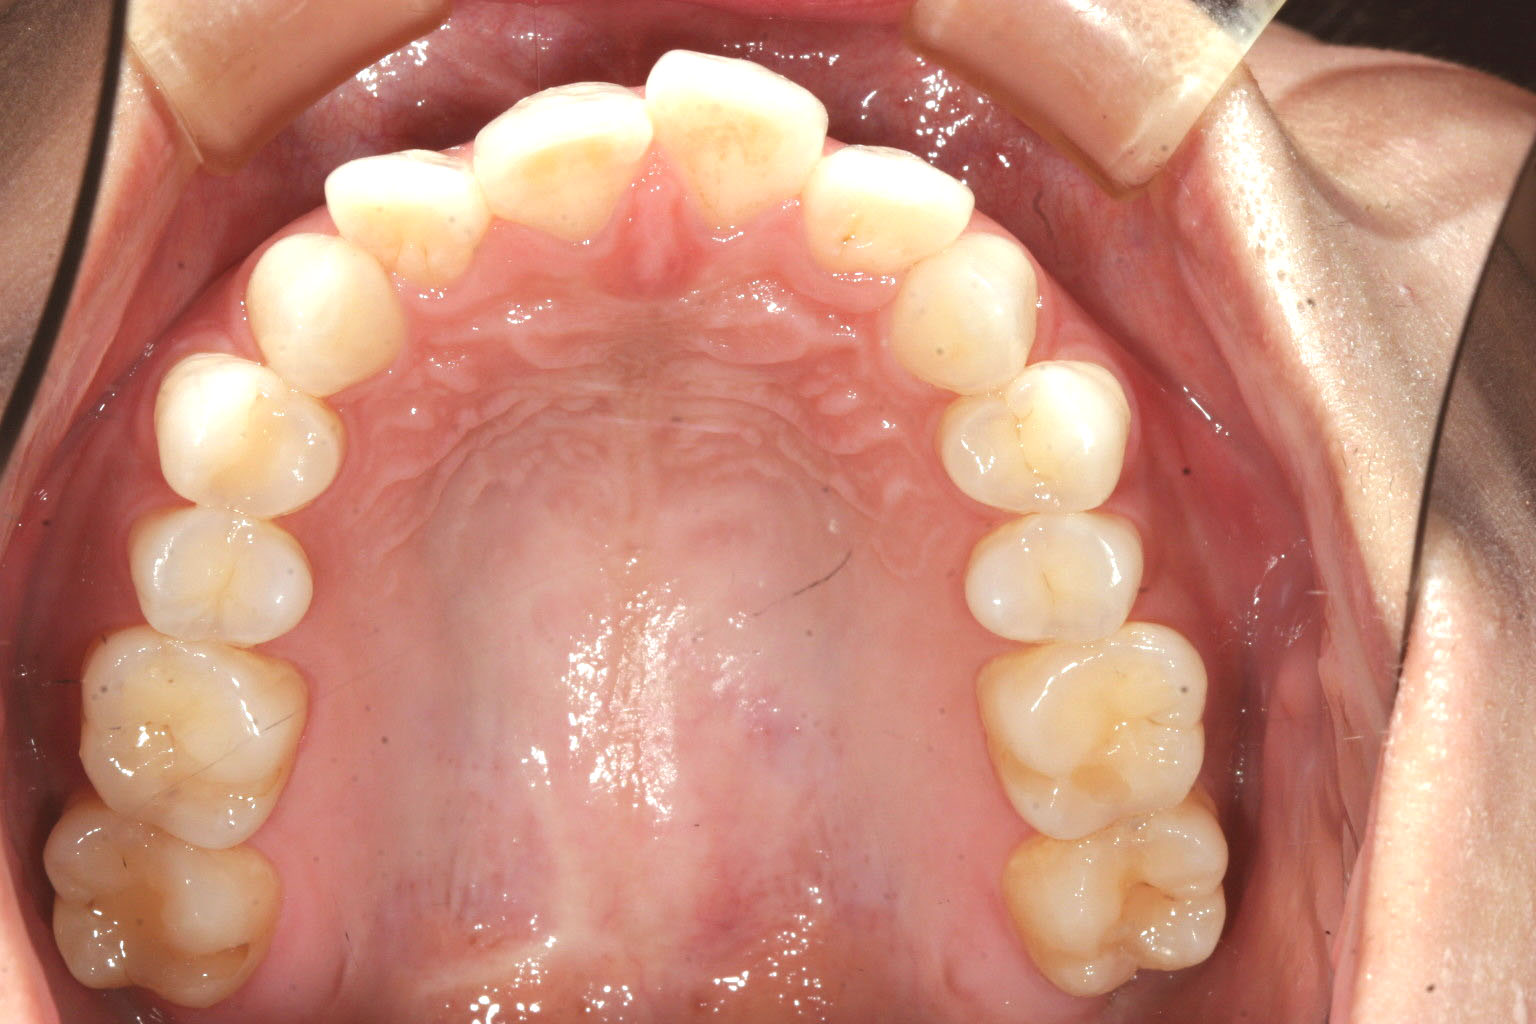

少しオーバージェットも大きいですね!

オーバージェットもこんなに綺麗に改善しました。 術前と比較してください。